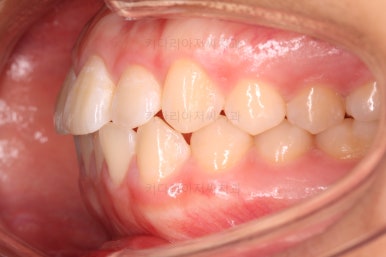

초진 시 입안의 모습이에요. 치열이 많이 나쁜 편은 아니고 앞니쪽이 조금 삐뚤어져 있네요.

특히 윗니 작은 앞니 하나가 아랫니보다 안으로 쑥 들어가 있어서 옆에 있는 송곳니가 덧니처럼 보여요.

라고 대부분 말씀 들을 하시지만 실제로 입 안을 보면 송곳니(덧니)가 많이 튀어나가 있기 보다는 옆에 있는 작은 앞니가 쏙 들어가서 상대적으로 튀어나와 보이는 경우가 대부분이에요.

이래나 저래나 덧니처럼 보이는 건 마찬가지이고, 공간을 확보하여 가지런하게 해줘야 하는 것도 사실이지만요.

입을 다물었을 때는 많이 심하진 않지만 돌출감이 있었어요.

환자분은 기왕 하는김에 돌출갇모 개선하고 싶어 하셨어요.